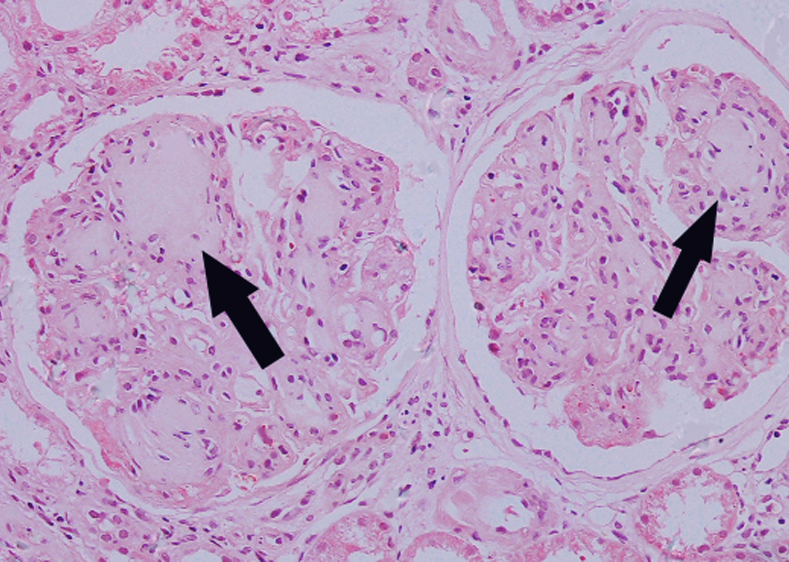

2.糖尿病肾病